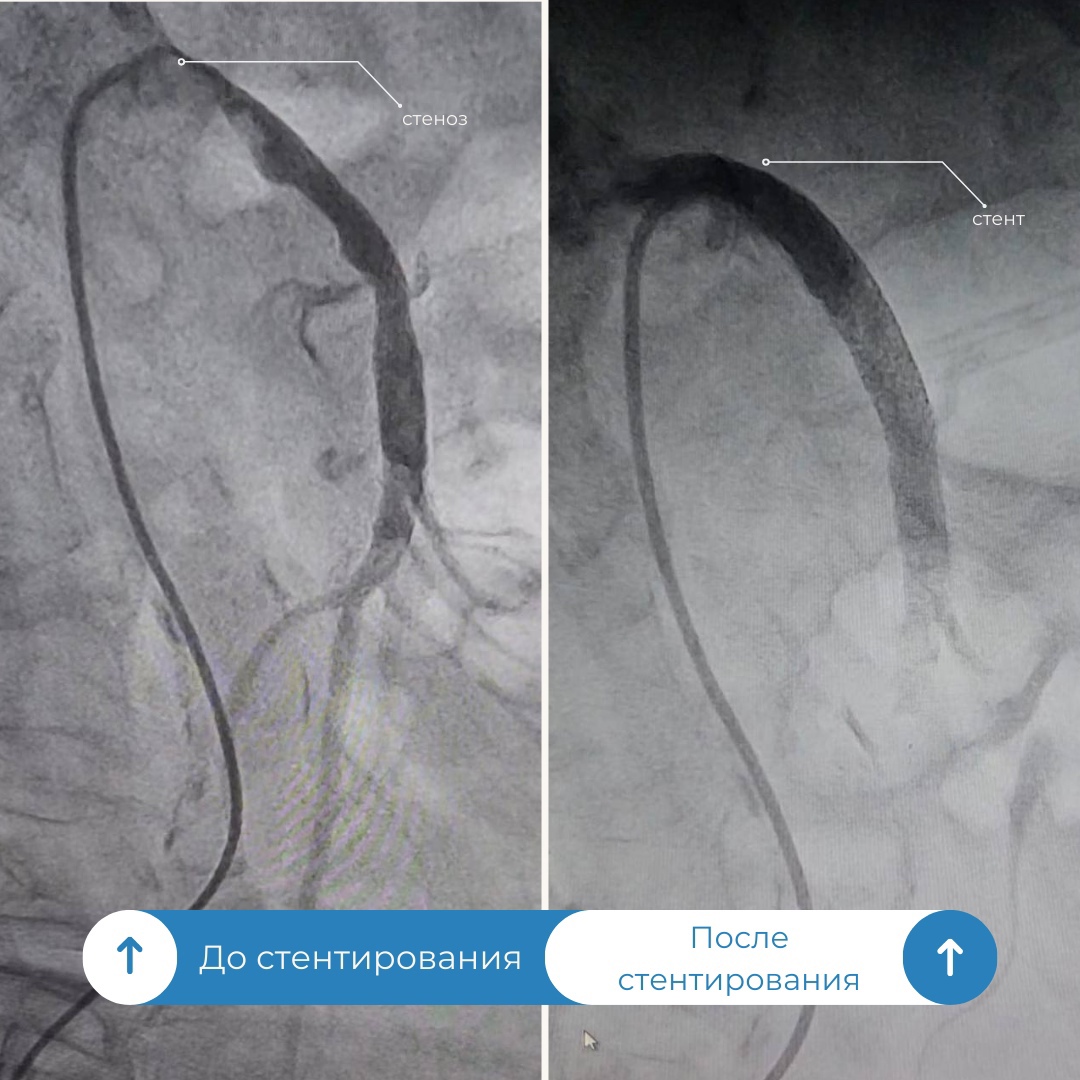

Врачи окружной Нижневартовской больницы успешно провели операцию у женщины с заболеванием, которое встречается у 2-4% пациентов. В приемный покой медучреждения поступила пациентка с жалобами на высокое давление и боли в животе и за грудиной. После проведения компьютерной томографии специалисты обнаружили сужение верхней брыжеечной артерии, которая снабжает кровью кишечник. Этот диагноз характеризуется высокой смертностью, которая колеблется в пределах 70-90%.

«Усугублялась ситуация и тем, что у пациентки наблюдался выраженный кальциноз, когда соли кальция откладываются на стенках сосудов. Поэтому было решено оценить варианты и возможности развития событий в рентген операционной. Через прокол в бедренной артерии в аорту мы ввели диагностический катетер и установили его в устье верхней брыжеечной артерии, затем ввели контрастное вещество и под рентген-контролем выявили критический стеноз» , – прокомментировал операцию врач по рентгенэндоваскулярному лечению Уйгунжон Жахонгиров.

Операция прошла успешно, боли прошли и кровообращение нормализовалось. На сегодняшний день женщина чувствует себя хорошо и уже находится дома.